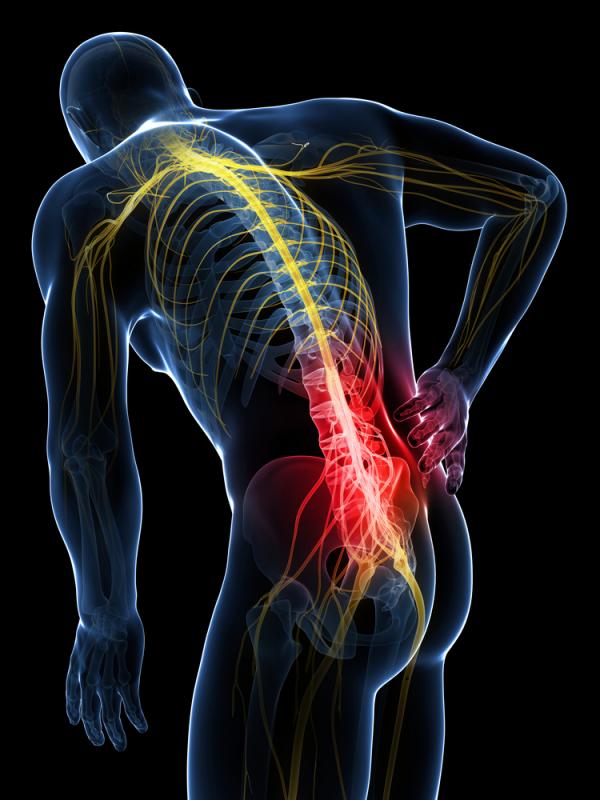

Back pain causes and treatment vary widely. Causes and treatment options can never be put into simple categories. Back pain causes involve a multitude of problems, from weak, tight and unstable muscles, degenerative structural changes, poor posture, unstable feet, etc the list is sometimes endless.

Chronic back pain may have many causes, but many cases of back pain are based on abnormal spinal alignment and movement and the degeneration of the muscles that support your spine. State-of-the-art physical therapy equipment, regenerative medicine injections and advanced chiropractic care can naturally return you to a pain free lifestyle.